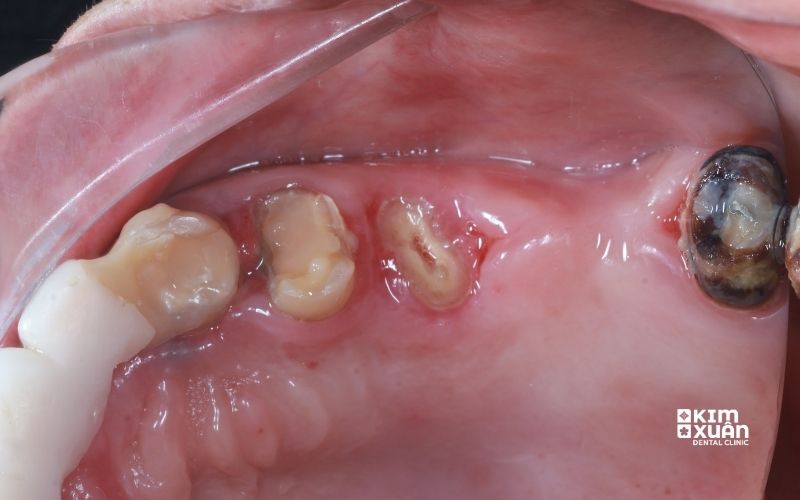

Còn chân răng là tình trạng thân răng đã mất hoàn toàn, chỉ còn lại phần chân răng nằm trong xương hàm. Tình trạng này thường xảy ra do:

Việc chỉ còn chân răng không chỉ khiến ăn nhai kém, mất thẩm mỹ, mà còn tiềm ẩn nhiều biến chứng nguy hiểm cho sức khỏe răng miệng, đặc biệt là nguy cơ tiêu xương hàm nếu để lâu ngày.

5. Những Nguy Cơ Tiềm Ẩn Khi Còn Chân Răng Nhưng Đã Bị Sâu

Khi phần chân răng còn sót lại bị sâu, khu vực này sẽ trở thành môi trường thuận lợi cho vi khuẩn phát triển và gây ra hàng loạt biến chứng nguy hiểm nếu không được xử lý sớm, bao gồm: